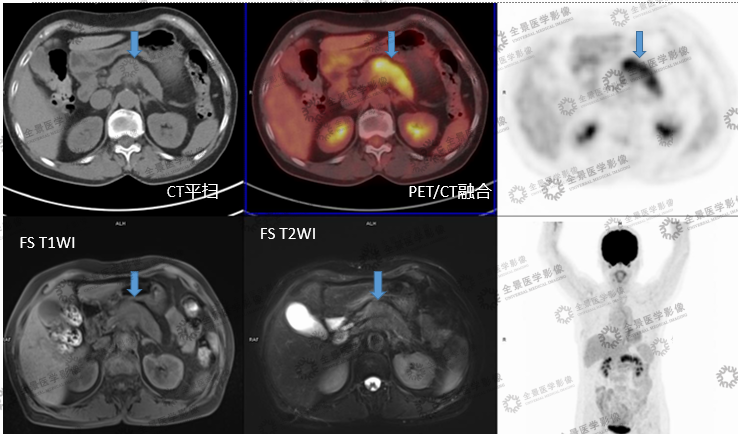

实例一

病史:女70岁 腹部不适,纳差半月,CT:胰腺MT伴小网膜囊淋巴结肿大及血管侵犯。

病灶呈延迟强化,FDG代谢增高,考虑胰腺癌。